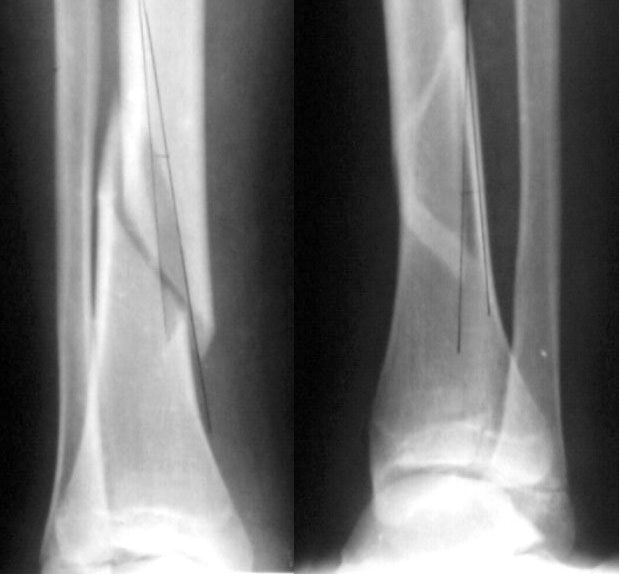

Девочка 14 лет полтора года назад оперирована в детской больнице по поводу спирального перелома костей голени (снимок 1)- выполнен закрытый остеосинтез стержнем Богданова, введенным ретроградно с медиальной стороны (снимок 2). Фиксатор после сращения удален

(см. снимки 3 и 4, после удаления, для сравнения со здоровой стороной, фас - стоя с нагрузкой на обе ноги). В настоящее время беспокоят боль и отеки в области голеностопного сустава при нагрузках, после ходьбы. В покое и ночью боли нет.Амплитуда движений в голеностопном суставе практически полная. Имеется заметная боковая нестабильность, т.е. несостоятельность дельтовидной связки и межберцоого синдесмоза. Складывается впечатление, что при остеосинтезе был отколот и смещен в сторону сустава костный фрагмент позади внутренней лодыжки, увеличилось смещение отломка заднего края, что привело к столь ранним проявлениям деформирующего артроза. Встает вопрос - что делать сейчас?Артодез - наверно, рано. Ревизию сустава, моделирующую резекцию?Пластику связок? Что-то еще? Заранее спасибо.

The retrograde IM device may have maintained a > 2mm displacement of the triplane fx which according to Ertl et al JBJS A 70: 967-976 1988

http://www.hwbf.org/hwb/conf/alex44/ertl.htm

generally gives a poor long term outcome.

Do you have access to injury films and what about bilateral comparative axial CT's to better define the ankle mortise pathoanatomy?